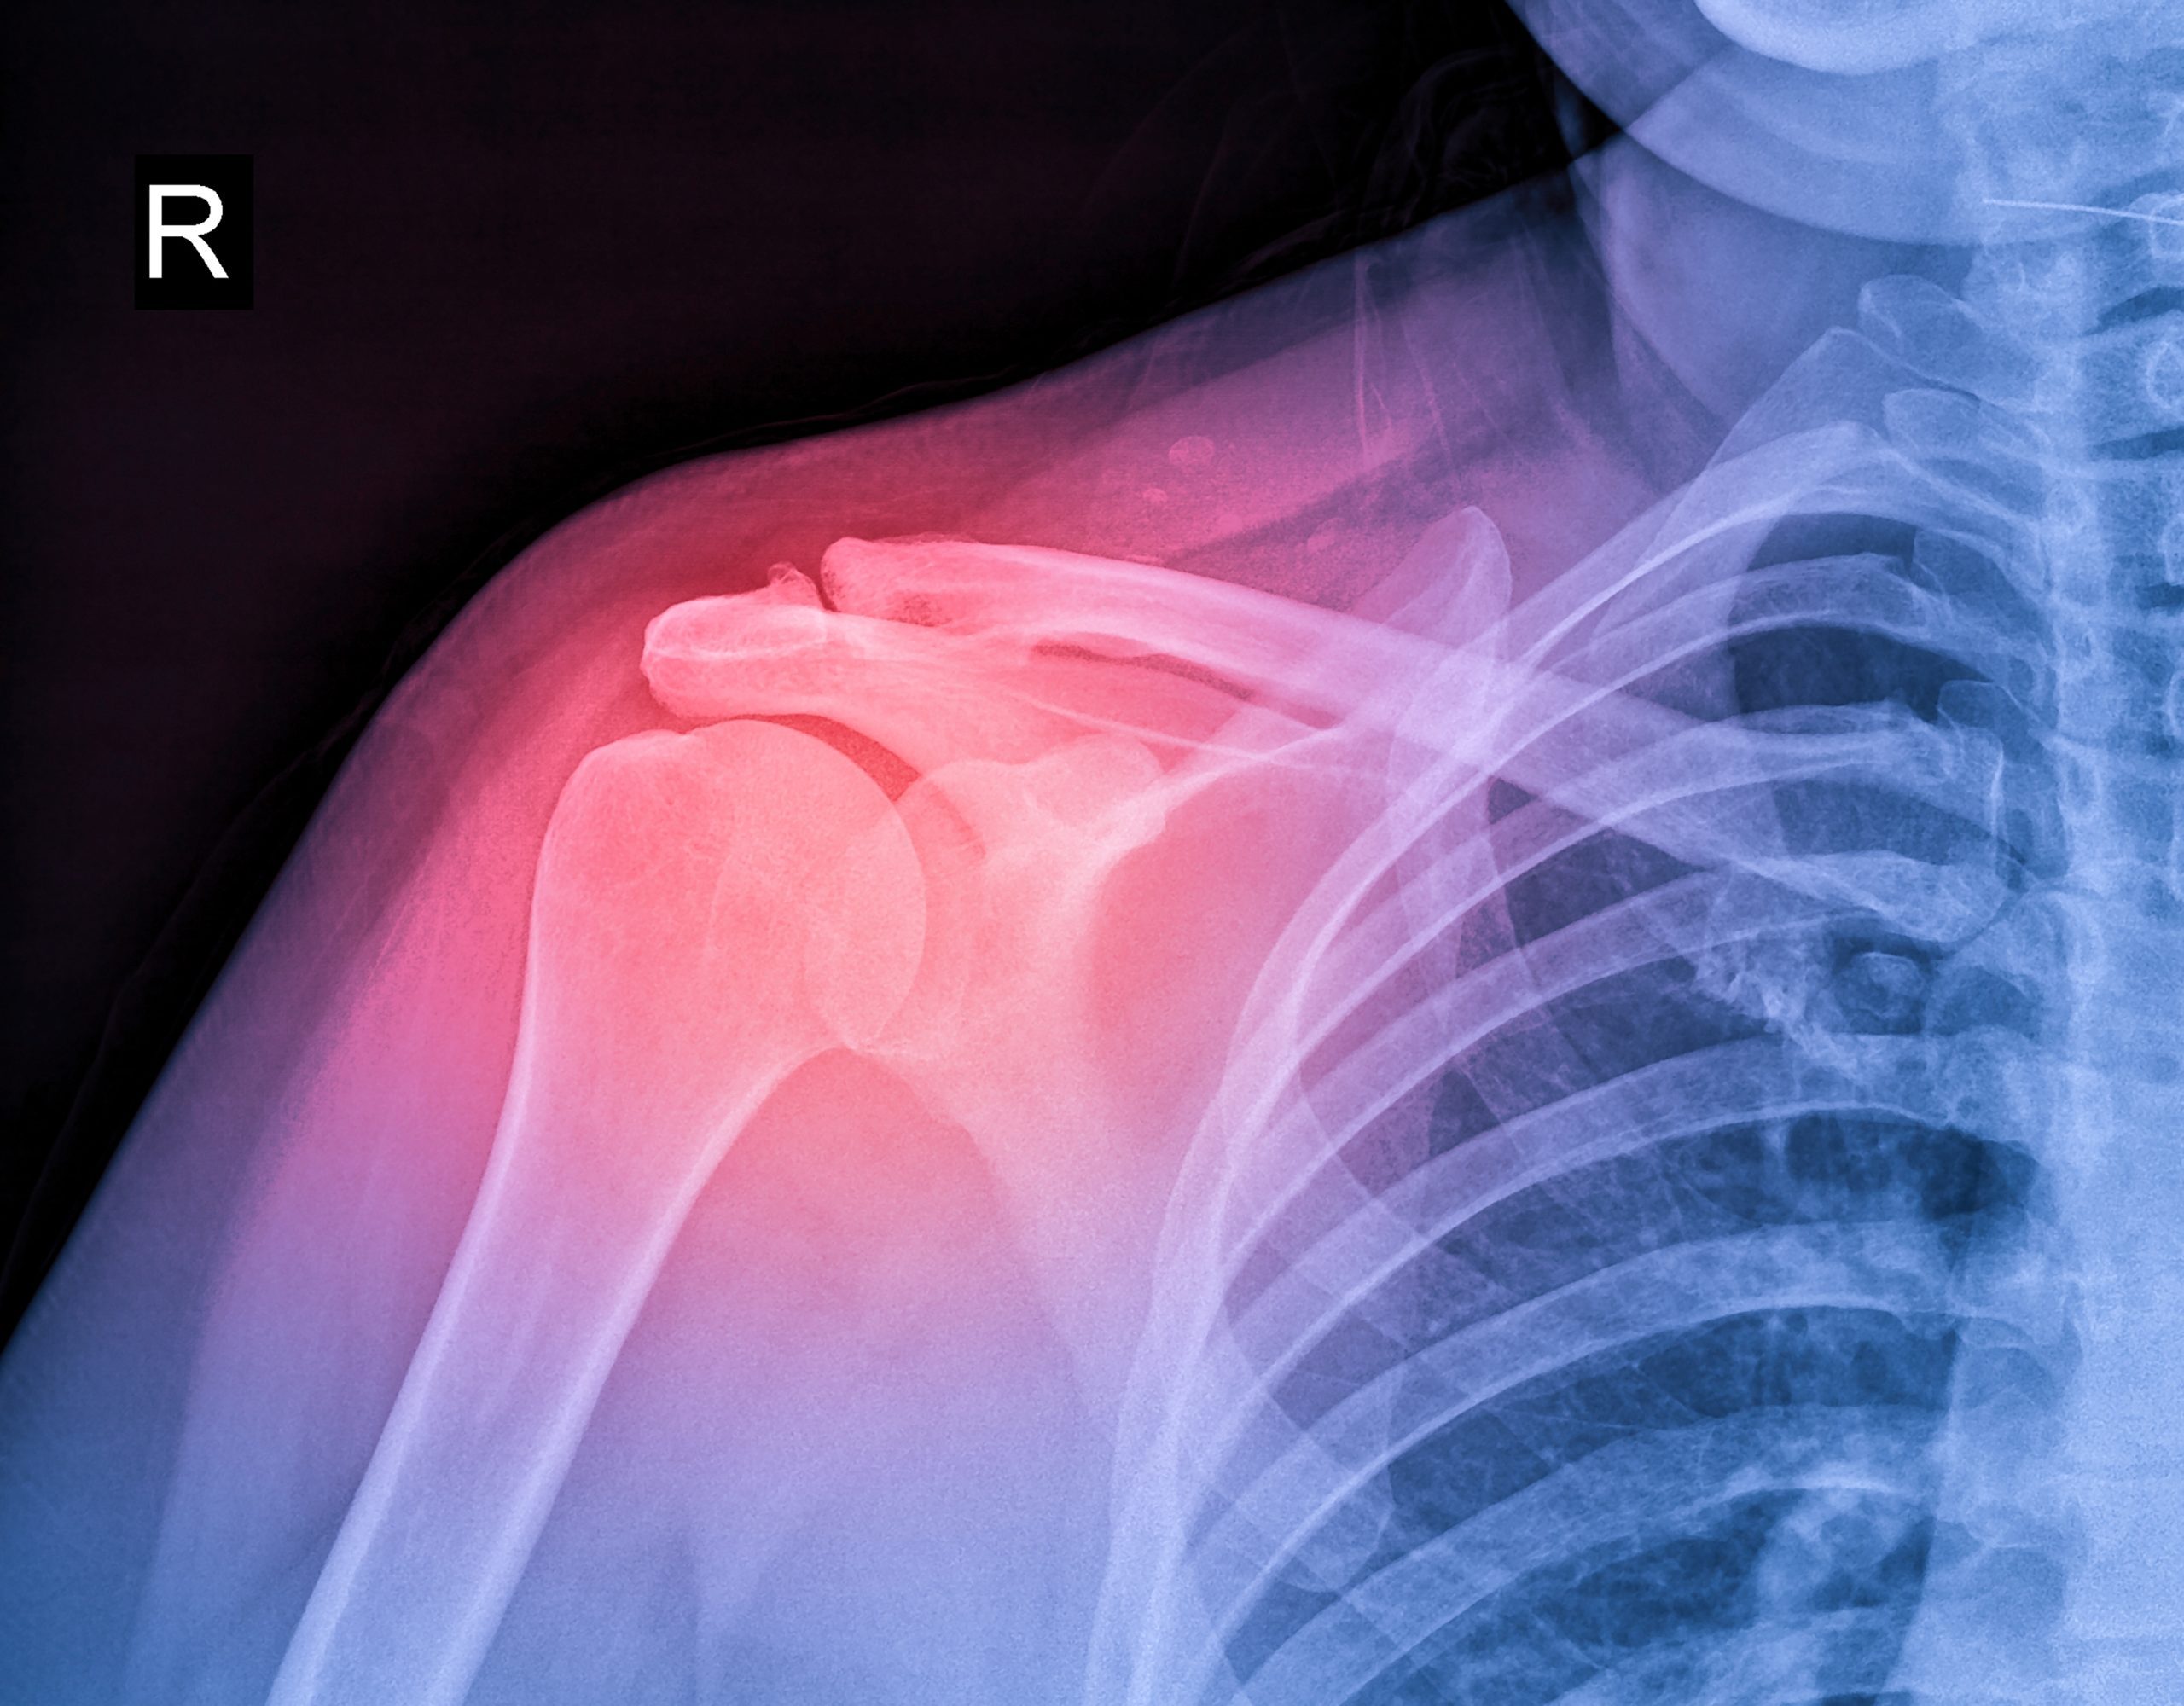

El hombro es la parte del cuerpo que sirve de nexo entre el brazo y el cuerpo. Es una articulación con una enorme complejidad y compuesta por distintas estructuras. Entre ellas se destaca la unión de tres huesos muy importantes: la clavícula, el omóplato y el húmero

El hombro es la articulación con mayor rango de movimiento de todo el cuerpo, lo que lo convierte en el más propenso a sufrir lesiones.

Un especialista en lesiones de hombro no solo es un doctor encargado de tratar dolores de hombro; sino también un experto en la compleja red de músculos, ligamentos y tendones que lo conforman.